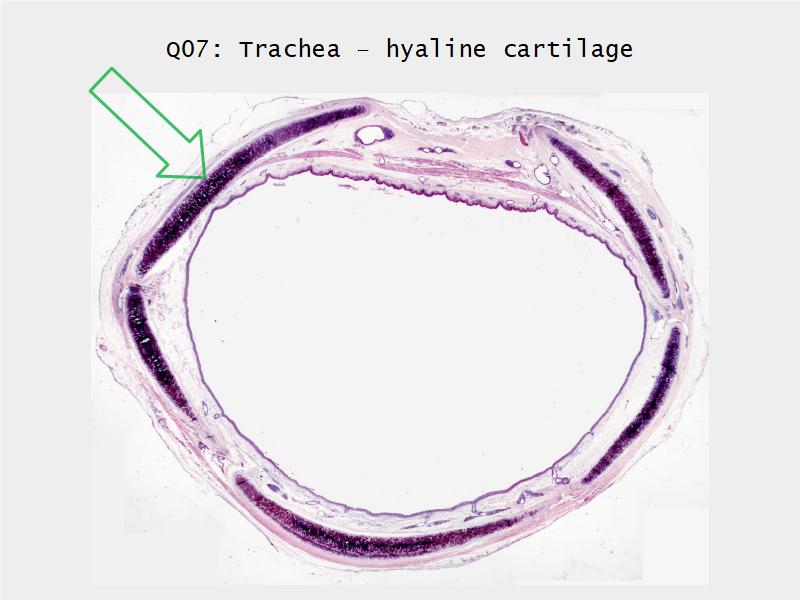

- Slide 73: Trachea